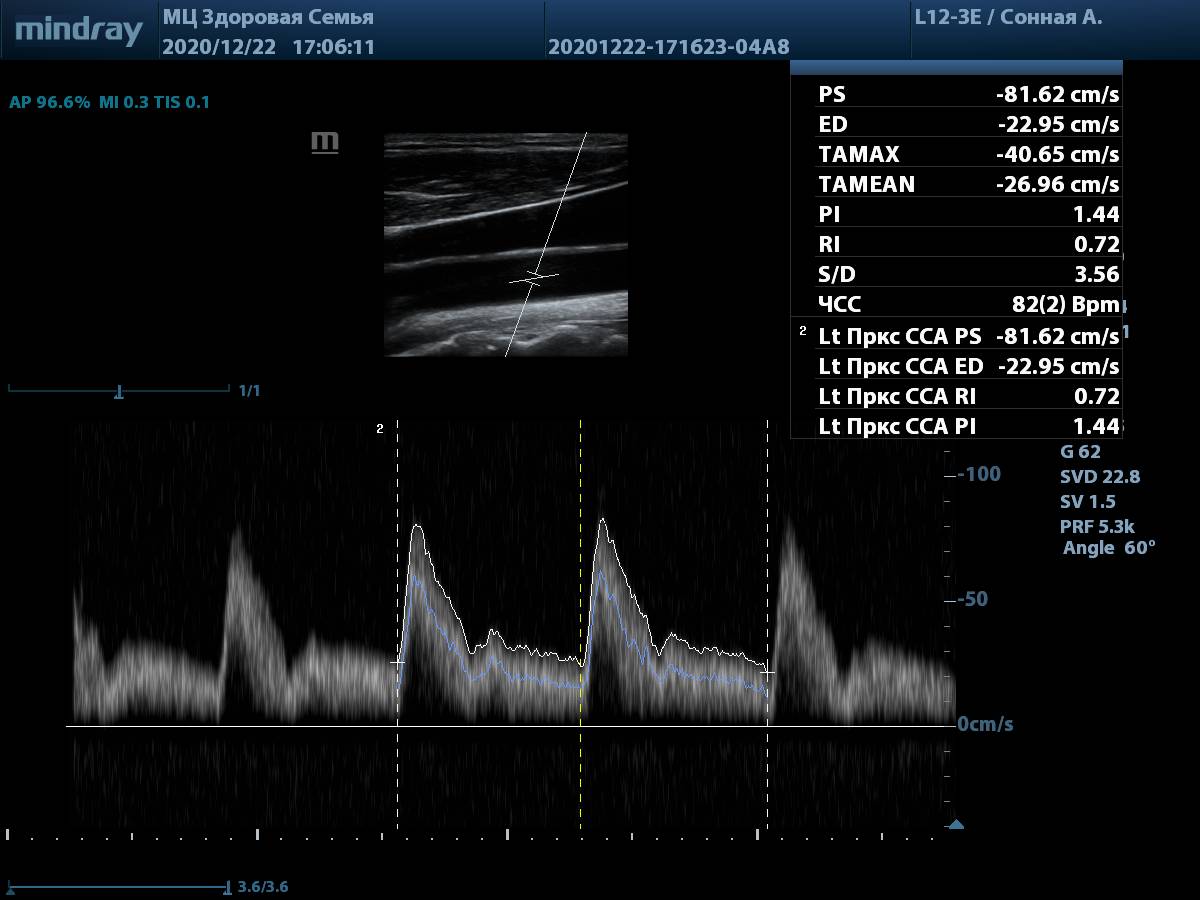

9. Общая сонная артерия, PW-допплер. Автоматическая трассировка игнорирует мелкие артефакты, четко повторяя спектр, а также использует несколько комплексов для снижения погрешности. Для отправки результата в отчет достаточно выбрать параметр в меню измерений.